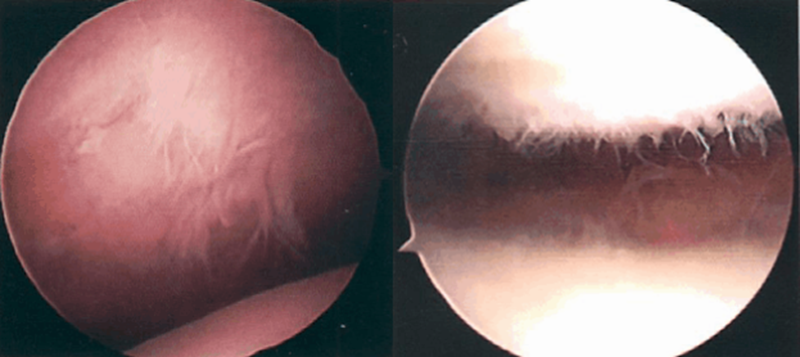

髌骨软化症Ⅲ级

髌骨软化症Ⅳ级

Ⅲ级:软骨的毛刷状或纤毛化改变达关节软骨厚度一半以上,直径>1.3cm,关节软骨表面类似蟹肉样改变,表面有多发软骨碎片附着其下的软骨。

Ⅳ级:关节软骨全层受侵,软骨下骨暴露,表现为进展期髌股关节炎。